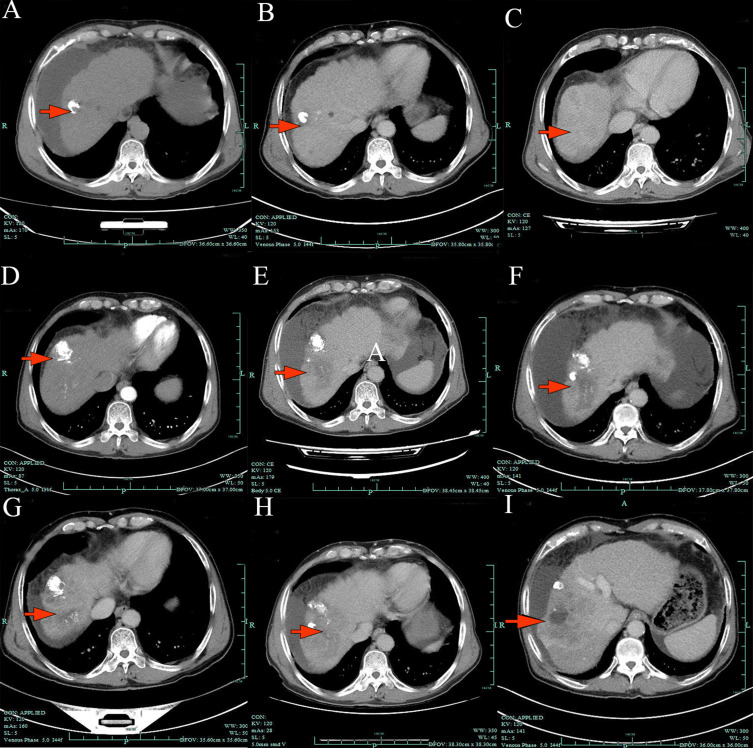

Case presentation: A 67-year-old male with HBV-related HCC (cT2N1M0, Child-Pugh B) exhibited rapid progression after transarterial chemoembolization, bevacizumab/sintilimab, and lenvatinib monotherapy. Salvage triplet therapy with bevacizumab (400 mg IV q3w), sintilimab (200 mg IV q3w), and lenvatinib (8 mg daily) achieved >50% alpha-fetoprotein (AFP) reduction within two cycles and sustained radiologic disease stabilization for 10 months, with only grade 1 fatigue and hemoptysis.

Conclusion: This is the first documented case of bevacizumab/sintilimab/lenvatinib triplet efficacy in triple-class refractory HCC, suggesting potential synergistic mechanisms and feasibility even in Child-Pugh B patients. These findings warrant further investigation in prospective studies.